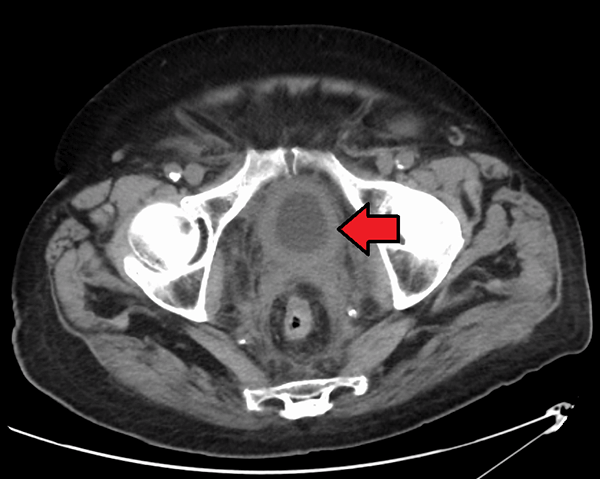

A CT scan from a patient with bladder cancer, showing disease-related thickening of the bladder wall.